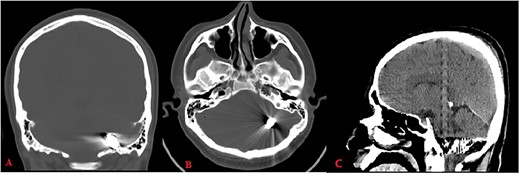

Pupils were equally reactive, and his vitals were stable. Cranial computerized tomography (CT) revealed a bone defect of 0.5 cm in the left parietal region and a metallic object located between left occipital bone and inferior side of left cerebellar hemisphere (Fig. 1).

Computed tomography (bone window: A: coronal, B: axial) reveals metallic object located between left occipital bone and inferior side of left cerebellar hemisphere; CT (brain window C: sagittal) shows hemorrhage along its trajectory.

The bullet had passed through the left parietal lobe. There was hemorrhage along its trajectory, but the metal artifacts obscured the damage. The entry wound was debrided and sutured.